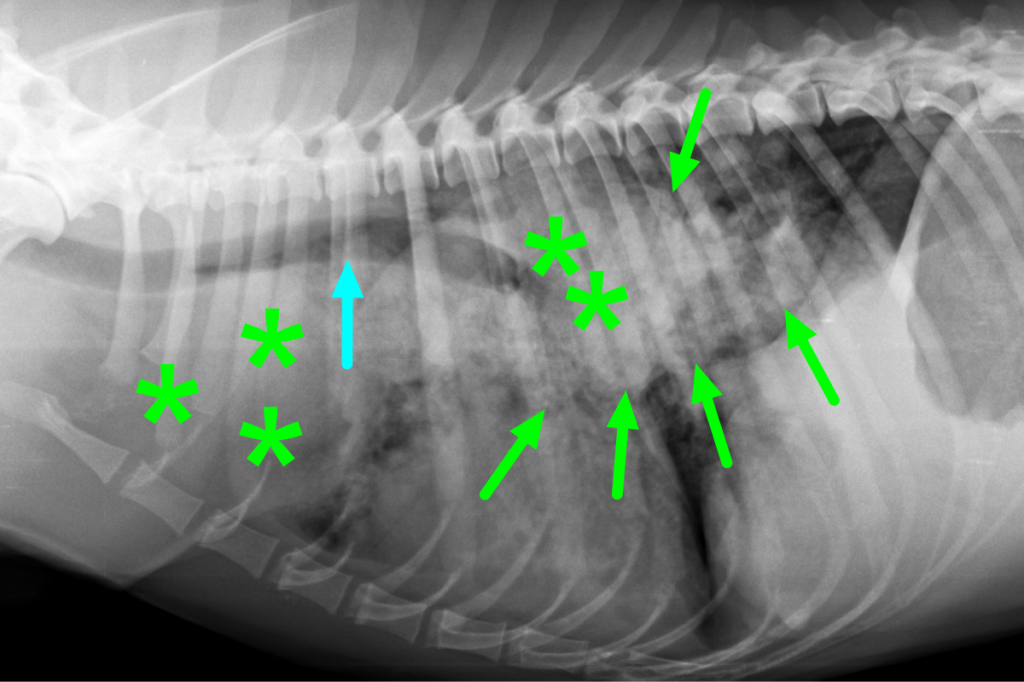

Если состояние вашего питомца стабильное, можно выполнить рентгенографию грудной клетки, положив собаку на спину. На этой рентгенограмме могут быть признаки отека легких, такие как повышенная интерстициальная или альвеолярная непрозрачность. У собак, страдающих кардиогенным отеком легких, также могут наблюдаться кардиомегалия и расширенные легочные вены.

Рентгеновские снимки являются основным инструментом для диагностики отека легких, поскольку они выявляют жидкость внутри легких собаки. Рентген также может выявить увеличенное сердце или другие аномалии сердечной мышцы.